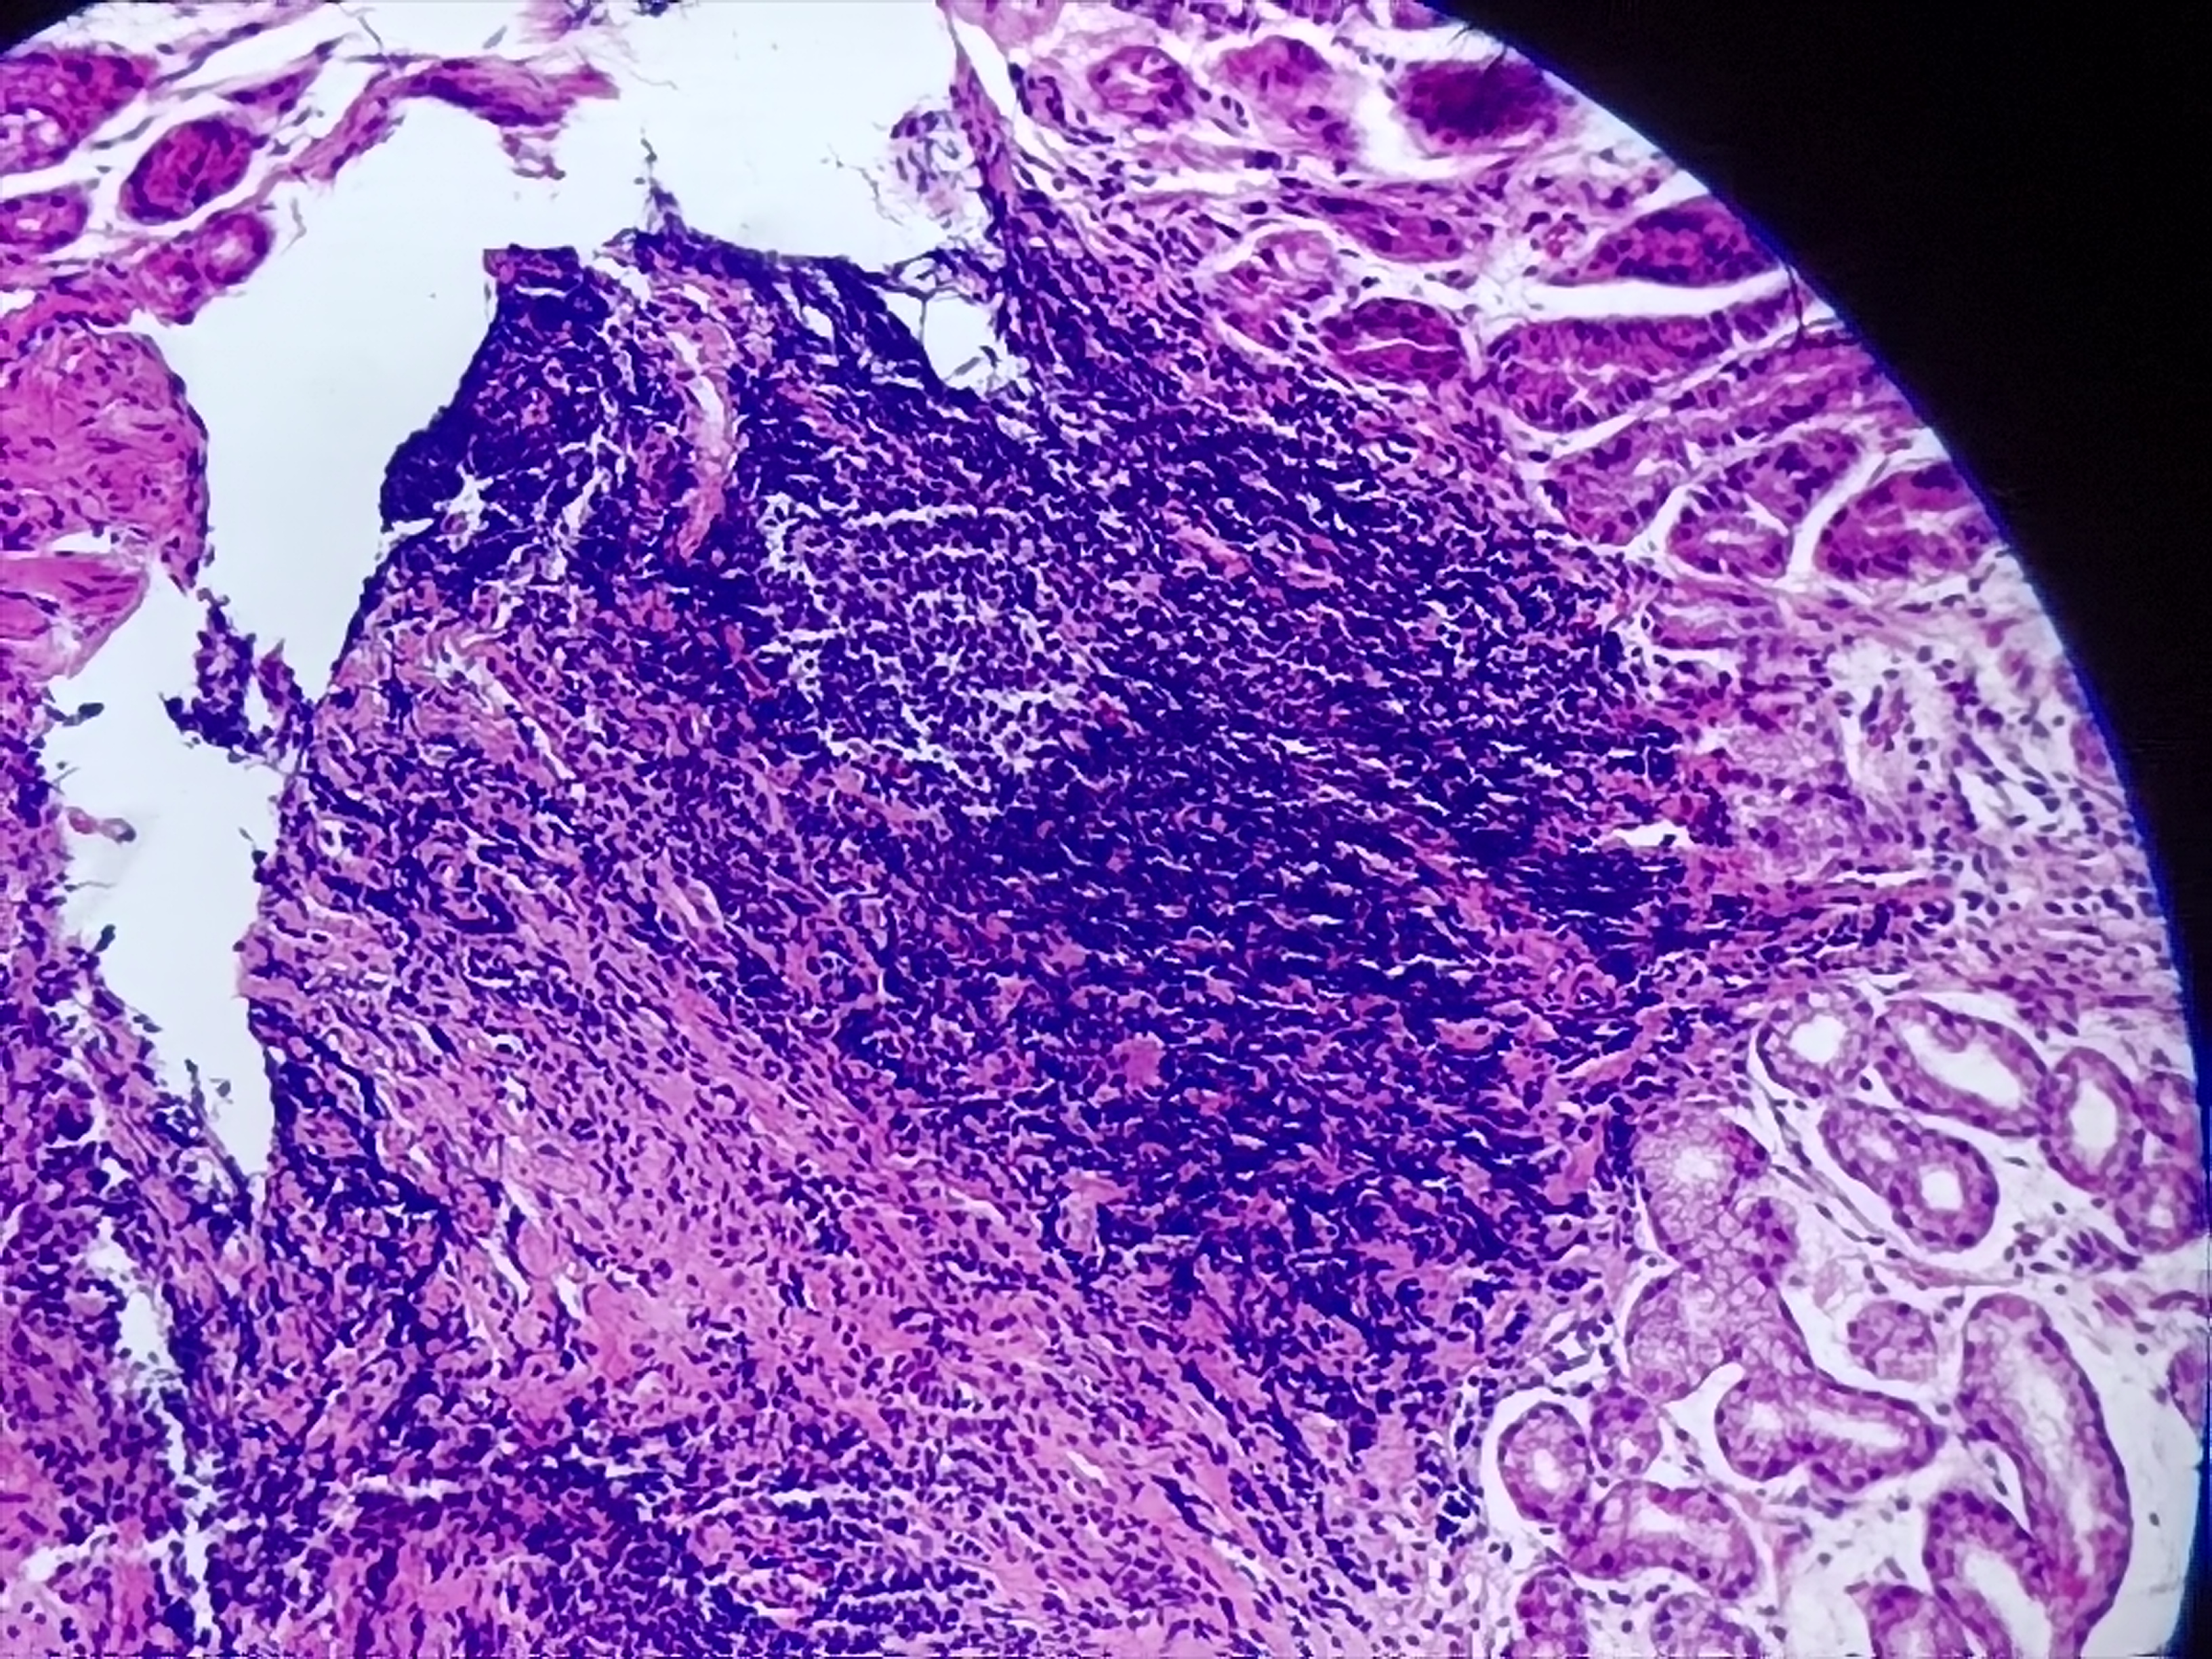

贲门活检

性别

男

年龄

20岁

临床诊断

一般病史

贲门可见糜烂

标本名称

贲门粘膜活检

大体所见

灰白色组织1块

粘膜慢性炎,鳞状上皮增生,固有层淋巴细胞聚集